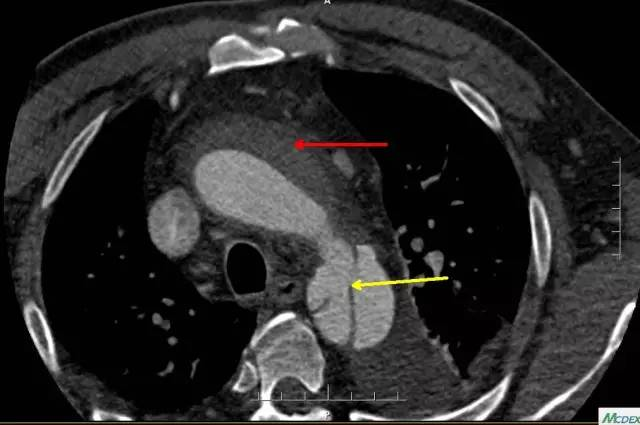

近端破口(黄箭头)及周围血肿(红箭头)

如此凶险的疾病,治疗就是跟时间赛跑。通过CT室开通的绿色通道,20分钟内即完成胸腹主动脉联合CTA检查。结果支持崔文军副主任医师的诊断,但糟糕的是这个病人的主动脉破口紧贴左侧锁骨下动脉,向上累及主动脉弓及升主动脉,向下一直撕裂至双侧髂动脉,右侧肾动脉闭塞,左侧肾动脉真假腔供血,存在急性肾功能衰竭及下肢缺血坏死风险!

这时王兵教授也赶到了病房,亲自查看患者,详细询问发病情况,仔细为患者体格检查。他带领大家仔细研读CTA结果:患者主动脉夹层诊断明确,目前,主动脉夹层首选腔内治疗,但患者主动脉破口紧贴左侧锁骨下动脉,并逆撕至锁骨下动脉,做为支架近端锚定区的升主动脉及主动脉弓全程壁间血肿。该类患者急性期不宜行支架植入,因为近端主动脉的血肿及水肿严重,植入的支架极易损伤血管内膜,导致新的夹层发生,一旦出现将导致手术失败,不仅增加再次手术的风险,死亡风险也大大增加!如果选择腔内治疗,必须等病人度过急性期,并动态行CTA检查,直至升主动脉及主动脉弓部血肿吸收后,方有机会进行支架植入。但该方案等待时间长,在等待过程中随时有主动脉夹层破裂出血导致死亡风险!另外的方案就是选择急诊开胸手术,行主动脉全弓人工血管置换术,但该术式创伤大,并发症相对较多,同时亦有较高的围手术期死亡率。